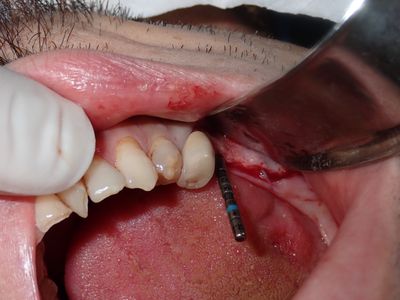

relatively straight forward implant placement, some bone expansion and countersinking. buccal bone thin, grafted with sticky bone from allograft folloewd by collagen mmebrane soaked in prf fluid, additional fibrin membrane used